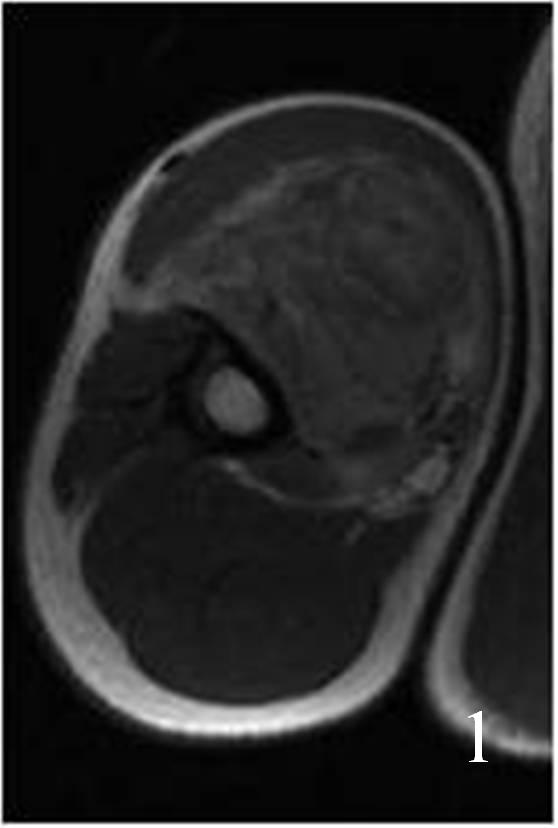

Fig. 1

Fig. 1-2: Axial (Fig. 1) and coronal (Fig. 2) MRI T1W of an angiosarcoma of the arm shows a well circumscribed heterogeneous lesion. Note the high signal in the center of the mass due to hemorrhage.